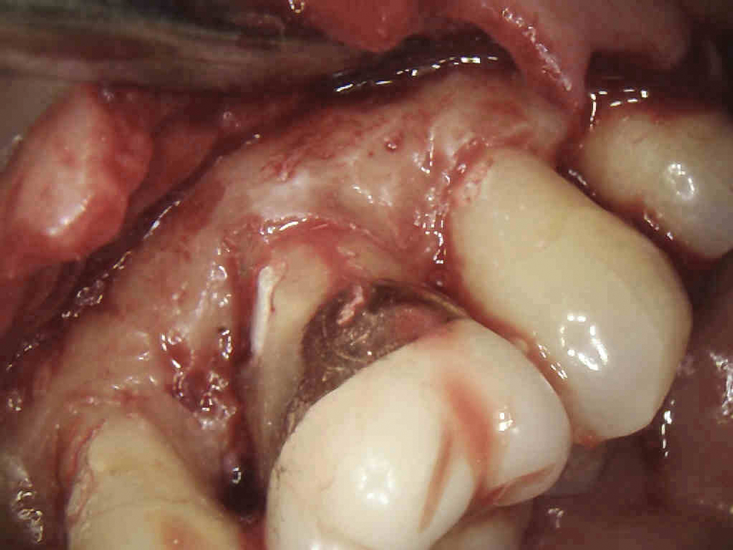

(3.) The initial surgical exposure revealed defects coronal to the crestal bone that were filled with granulation tissue and consistent with ECR.

Figure 3

The surgical repair of ECR lesions is relatively straightforward. First, a sulcular incision should be created to develop a full-thickness flap that allows for complete visualization of the resorptive defect. Subsequently, all of the resorptive tissue should be removed. Curette instrument options for resorptive tissue removal may include appropriately sized excavators, scalers, or a diamond bur in a high-speed handpiece. Next, the resorptive cavity should be cleaned, and any areas of thin dentin that prevent access to the depth of the lesion should be removed with a high-speed bur or an ultrasonic scaler. If the margin of the resorptive defect sits at the crestal bone, judicious removal of the crestal bone via crown lengthening may be necessary to avoid biologic width violation.6